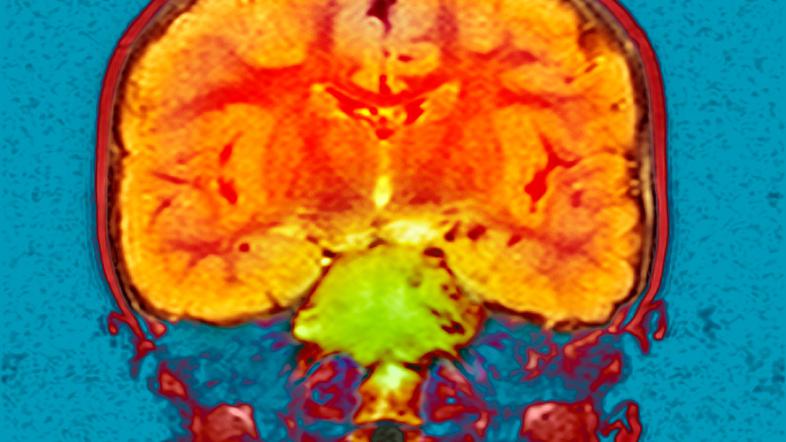

Diagnozo možganskega tumorja mogoče postaviti že z uporabo običajnih preiskav krvi. "Ugotovljena občutljivost metode je podobna občutljivosti slikovnih preiskav, kar odpira povsem nove možnosti v diagnostiki teh pomembnih nevroloških bolezni," navajajo naši raziskovalci v prestižni znanstveni reviji.

Možganski tumorji so k sreči relativno redke, vendar pogosto usodne bolezni. Njihovo odkrivanje je zahtevno, saj se pogosto pojavljajo z zelo neznačilnimi težavami, kot sta glavobol, spremeni se tudi osebnost človeka. Diagnostika te hude bolezni običajno temelji na klinični sliki in slikovni diagnostiki, pojasnjujejo na UKC Ljubljana.